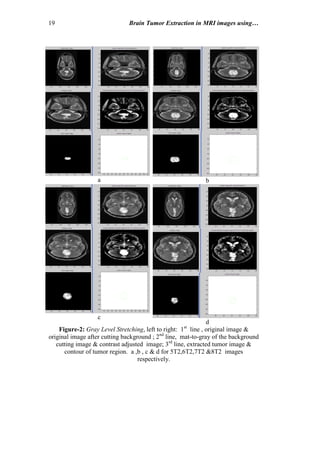

Figure-2: Gray Level Stretching, left to right: 1st

line , original image &

original image after cutting background ; 2nd

line, mat-to-gray of the background

cutting image & contrast adjusted image; 3rd

line, extracted tumor image &

contour of tumor region. a ,b , c & d for 5T2,6T2,7T2 &8T2 images

respectively.